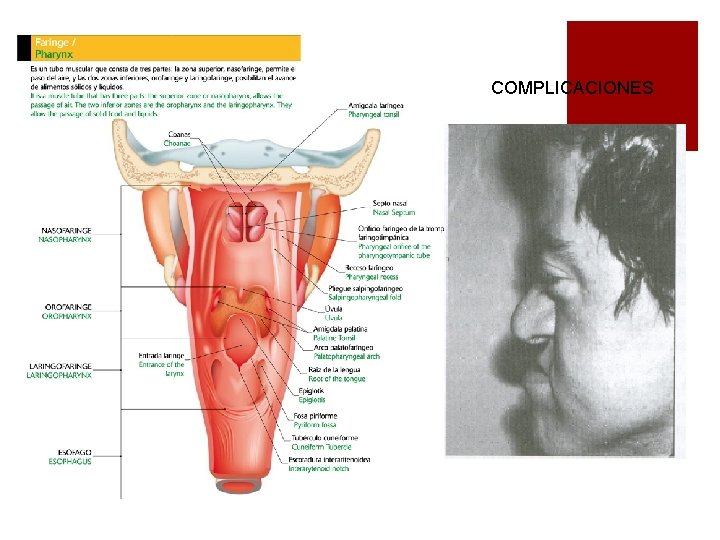

COMPLICACIONES